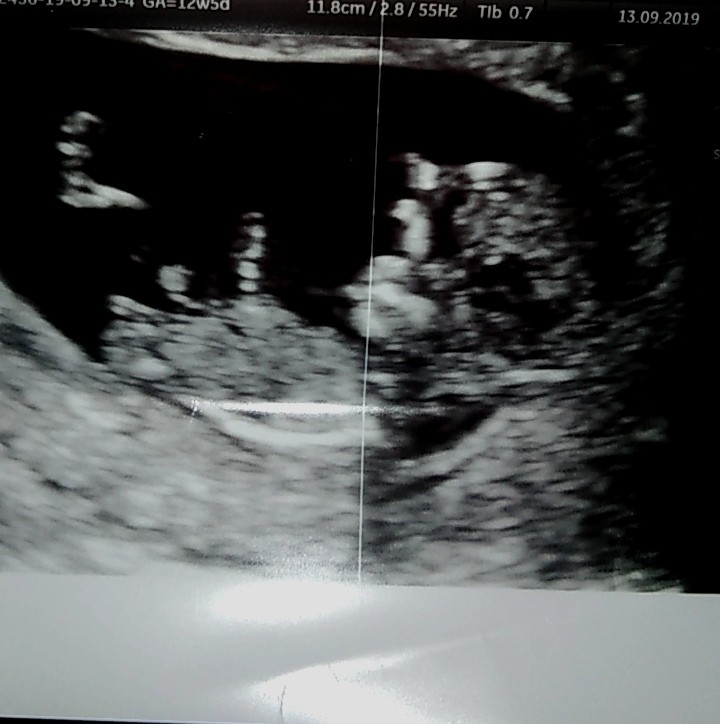

Ciąża, płeć zdjęcie usg

Czy widać na tym usg płeć dziecka?

Czy oznacz ia na usg, oraz karcie po badaniu prenatalnym w SEX: FEMALE

Oznacza płeć dziecka czy po prostu osoby badanej?

Wydaje mi się, że chodzi o osobę badaną. W karcie raczej nigdzie nie będzie zapisane, że to dziewczynka czy chłopiec. Nie każdy rodzic życzy sobie wiedzieć. Poza tym 12 tydzień to za wcześnie aby coś stwierdzić na 100 %. A ze zdjęcia nie widać nic.

Z tego zdjęcia ,nie da się nic zobaczyć , jak piszą dziewczyny 12 tc to za wcześnie ,dowiesz się koło 15/16 ,cierpliwości to tylko miesiąc ,zleci raz dwa

Dziewczyny, nie piszcie, że poznanie płci jest niemożliwe w 12tc, bo ja w obu ciążach poznałam płeć na pierwszym USG prenatalnym i nie, nie był to strzał, bo w obu ciążach byłam na dwóch USG pod rząd u dwóch różnych lekarzy. Po prostu dobry sprzęt i dobry lekarz.

Natomiast na zdjęciu USG autorki postu to ja buźkę widzę, a nie narządy :D

Płeć można określić na podstawie położenia nuba czyli wyrostka płciowego. U dziewczynek jest równoległy do kręgosłupa, u chłopców się unosi pod kątem 45 stopni. Z tego usg obstawiałabym w 85% dziewczynkę. :)